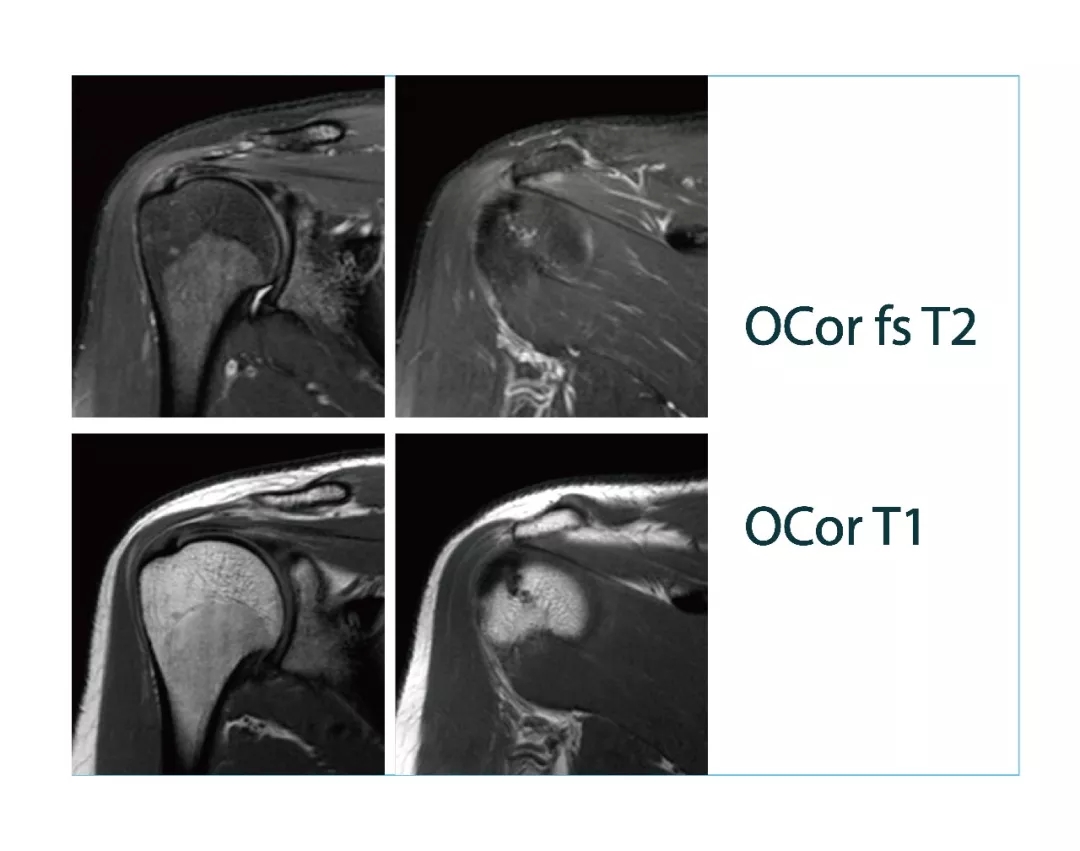

【朗润影像档案】磁共振影像病例分享(编号20180316)